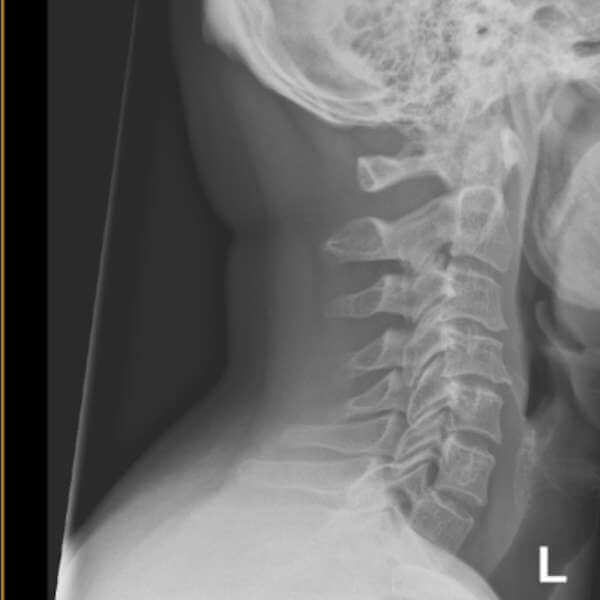

Πρόσθια αυχενική δισκεκτομή

Η πρόσθια αυχενική δισκεκτομή με συνοδό αρθροπλαστική ή οστεοσύνθεση περιλαμβάνει αντικατάσταση του φθαρμένου δίσκου από τεχνητό δίσκο, ή κλωβό προκειμένου να επιφέρει την αποσυμπίεση του νωτιαίου μυελού και των εξερχόμενων νευρικών ριζών και να διατηρήσει την κινητικότητα στο προσβεβλημένο επίπεδο, ή να σταθεροποιήσει την περιοχή.

Η επέμβαση γίνεται με μια μικρή τομή 2,5 εκ. στο λαιμό. Η προσπέλαση γίνεται με την βοήθεια του μικροσκοπίου, αφαιρείται ο δίσκος και τα οστεόφυτα που πιέζουν τις νευρικές δομές. Ο δίσκος αντικαθίσταται ανάλογα με την περίπτωση είτε με τεχνητό δίσκο (αυχενική αρθροπλαστική), ή με ένα ειδικό κλωβό, ο οποίος είναι γεμάτος με οστικό μόσχευμα (αυτομόσχευμα ή αλλομόσχευμα). Ο τεχνητός δίσκος τοποθετείται μόνο σε περίπτωση που ο ασθενής έχει μέχρι το πολύ σε δύο γειτονικά επίπεδα βλάβη του δίσκου, χωρίς άλλες εκφυλιστικές αλλοιώσεις και χωρίς ιστορικό οστεοπόρωσης.

Οπίσθια αυχενική δισκεκτομή

Η οπίσθια αυχενική δισκεκτομή ή οπίσθια τρηματεκτομή κατά Frykholm εφαρμόζεται συχνότερα για δισκοκήλες που βρίσκονται στα πλάγια του νωτιαίου μυελού ή σε μονόπλευρες στενώσεις του μεσοσπονδύλιου τρήματος. Είναι η χειρουργική επέμβαση κατά την οποία αφαιρείται ο σπασμένος ή εκφυλισμένος δίσκος ο οποίος πιέζει κάποιο νεύρο στον αυχένα, μέσω μιας μικρής τομής στον αυχένα (πίσω μέρος) του ασθενούς Η οπίσθια δισκεκτομή είναι λιγότερο επεμβατική από την πρόσθια, διότι δεν αφαιρείται ολόκληρος ο δίσκος αλλά μόνο το σπασμένο τμήμα του, έχει όμως συγκεκριμένες ενδείξεις.

Η επέμβαση γίνεται υπό γενική αναισθησία με τον ασθενή σε πρηνή θέση. Διενεργείται μια τομή 1,5 εκ. στην οπίσθια επιφάνεια του αυχένα. Τοποθετείται ένας διαστολέας και στη συνέχεια διανοίγεται το μεσοσπονδυλικό τρήμα και αφαιρείται το μικρό κομμάτι του οστού, ή στην περίπτωση δισκοκήλης, το τμήμα του δίσκου το οποίο πιέζει το νεύρο. Ακολούθως, κλείνει το τραύμα.